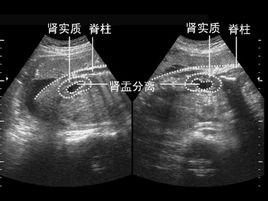

腎盂簡單的說就是腎和輸尿管連線的地方。腎盂擴張分離是由於腎結石、輸尿管畸形,導致尿液無法正常排出,於是腎盂被充盈變大形成的。當胎兒憋尿時,也可以發生腎盂分離。

一般來說如果腎盂分離不超過10mm,是屬於正常範圍的.如果胎兒出生時不大於16mm,也不會有什麼問題,如果繼續增大就要定期複查或考慮治療。

腎盂分離是孕婦產檢時,可能出現的一項檢查結果。一般腎盂分離不超過10mm為正常現象。腎盂分離90%是發生在男嬰身上的,有的寶寶到出生的時候拉泡尿就解決了這個問題。 有的寶寶是因為先天的尿路(排尿不暢,積壓在腎臟里)問題出來後要經過手術才能解決。